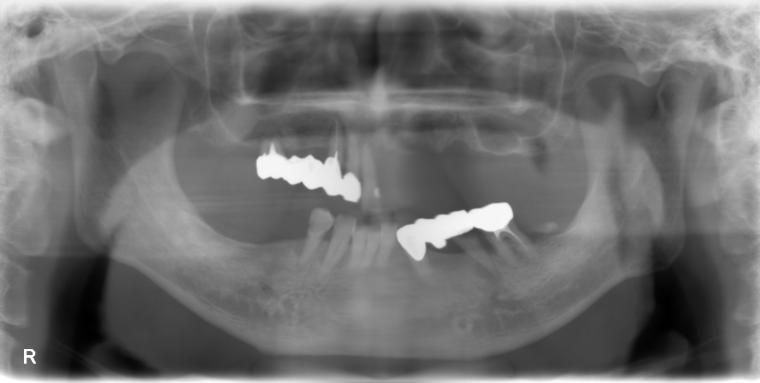

Before

62歳男性/オールオン4・6症例/インプラント埋込手術

オールオン4・6というインプラント義歯での治療を選択されました。